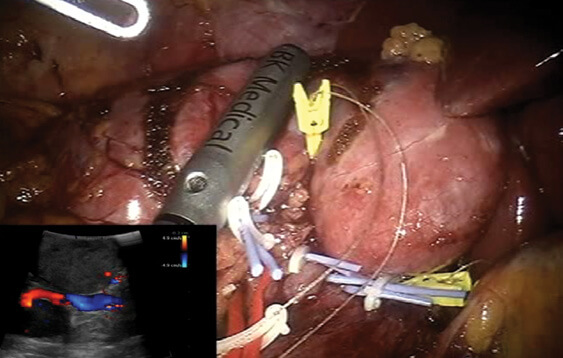

Ο ρομποτικός υπέρηχος ενσωματώνεται στον ρομποτικό βραχίονα και καθοδηγείται από την κονσόλα του χειρουργού. Αυτό έχει ως αποτέλεσμα μεγάλη ελευθερία κίνησης αλλά και διείσδυσης της κεφαλής του υπερήχου σε δύσκολα ανατομικά σημεία. Η σύγχρονη ποιότητα απεικόνισης προσφέρει υψηλή ευκρίνεια και καλύτερη πρόσβαση διεγχειρητικά, στα επιθυμητά σημεία.

Στους κακοήθεις όγκους του νεφρού, ειδικά στους μικρούς όγκους όπου υπάρχει ένδειξη για ρομποτική μερική νεφρεκτομή, η εφαρμογή των ρομποτικών υπερήχων προσφέρει πολύτιμη βοήθεια. Η ρομποτική μερική νεφρεκτομή, ακόμα και όταν εκτελείται από έμπειρο ρομποτικό χειρουργό, αποτελεί μια δύσκολη τεχνικά επέμβαση. Εδικότερα, μικροί όγκοι που εντοπίζονται κοντά στα αγγεία ή που βρίσκονται «κρυμμένοι» μέσα στο νεφρό χωρίς να εξέχουν από την επιφάνειά του, έχουν μεγάλο βαθμό δυσκολίας στην εξαίρεσή τους. Εδώ ακριβώς η χρήση του ρομποτικού υπερήχου κάνει τη διαφορά, ενισχύοντας τις δυνατότητες που μας προσφέρει η ρομποτική χειρουργική. Η εφαρμογή του υπερήχου εξαλείφει το μειονέκτημα της έλλειψης της αφής των δομών εντός του σώματος, αναγνωρίζει με ακρίβεια την εντόπιση του όγκου αλλά και τα αγγεία που τον αιματώνουν, αναγνωρίζει τα όρια του όγκου έτσι ώστε η εκτομή του να γίνει επί υγιών ορίων, μειώνοντας έτσι την πιθανότητα υποτροπής. Ο χειρουργός μέσω του υπερήχου «βλέπει» μέσα στο νεφρό και αφαιρεί τον όγκο διατηρώντας ταυτόχρονα το μεγαλύτερο τμήμα του οργάνου.